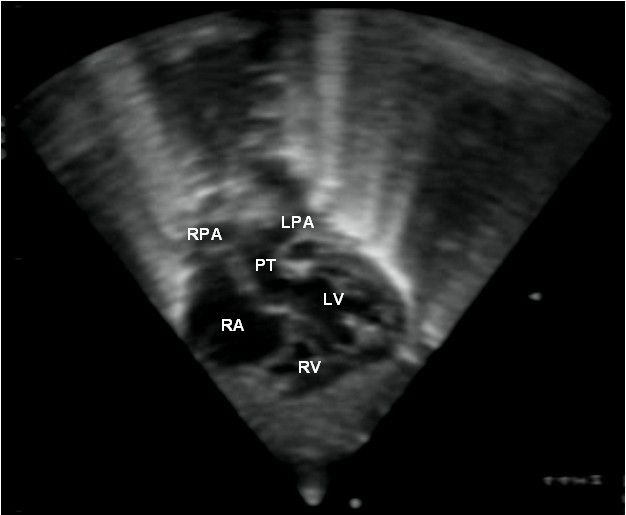

심장 초음파 검사는 심장의 구조와 기능을 정확하게 평가하는 초음파 검사이며, TGA의 특징을 보여줄 수 있다. 이 검사를 통해 TGA를 확진할 수 있다.[3]

약어: LV 및 RV=좌심실 및 우심실, PT=폐동맥, VSD=심실 중격 결손, PS=폐동맥 협착.]]